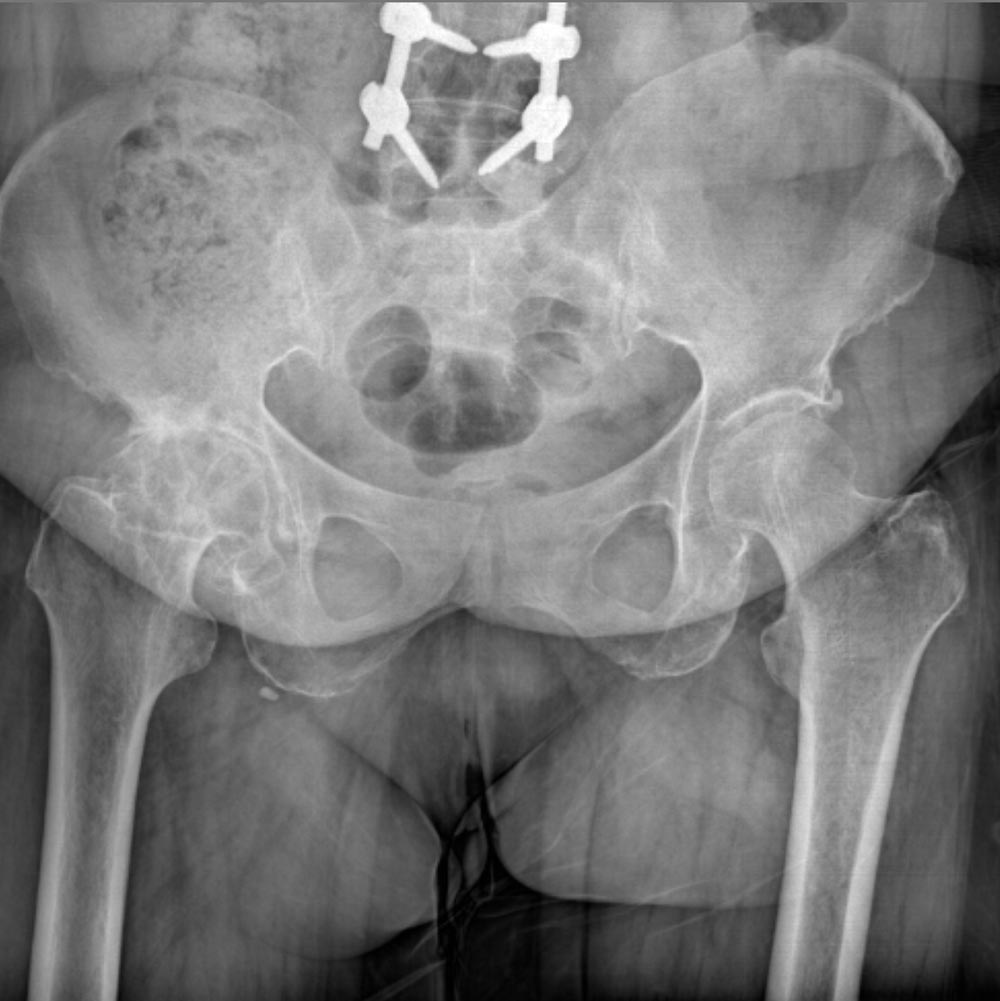

در نهایت، روش های تصویر برداری مثل رادیوگرافی به تشخیص بیماری کمک میکند. مهمترین روش تصویربرداری برای تشخیص ساییدگی لگن رادیوگرافی ساده است. تشخیص این بیماری نیاز به سی تی اسکن یا ام ار آی ندارد.

در تصویر رادیوگرافی از مفصل، چون غضروف نازک شده است فاصله مفصلی یا فاصله بین دو استخوانی که مفصل را تشکیل داده اند و در حد چند میلیمتر است کاهش پیدا میکند و در کناره های استخوان های تشکیل دهنده مفصل استخوان اضافی دیده میشود.

همچنین ممکن است کیست های استخوانی در بالای استابولوم یا در سر استخوان ران دیده شود.

در زیر تصاویری از عکس ساییدگی لگن در چند بیمار را میبینید. با کلیک بر روی هر کدام تصویر بزرگتری از آن را خواهید دید.

در این روش با استفاده از ابزارهای خاص، استخوان لگن یا استخوان بالای ران را در قسمت های معینی برش داده و سپس استخوان را در وضعیت جدیدی قرار داده و با پیچ و پلاک در وضعیت جدید محکم میکنند.

بعد از مدتی استخوان در وضعیت جدید جوش میخورد. پس هدف از این نوع جراحی تغییر وضعیت استخوان است. و هدف از این تغییر وضعیت اینست که توزیع نیروهایی را که به مفصل ران وارد میشود تغییر دهیم.